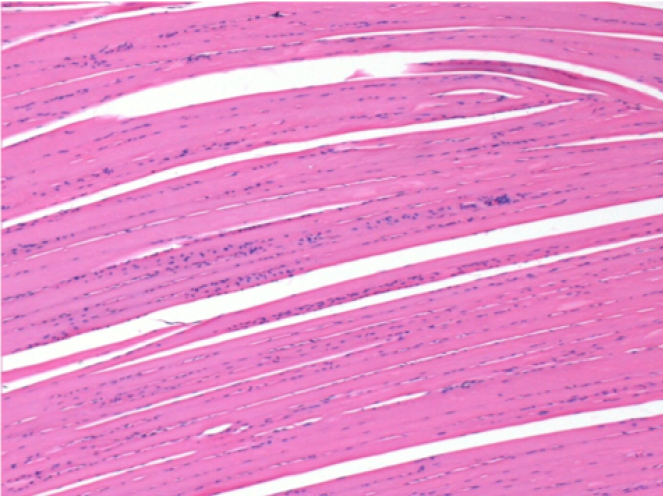

Через 3 місяці (90 днів) після ін'єкції Ендопіл 0,1 мл в правий претибіальний м'яз.